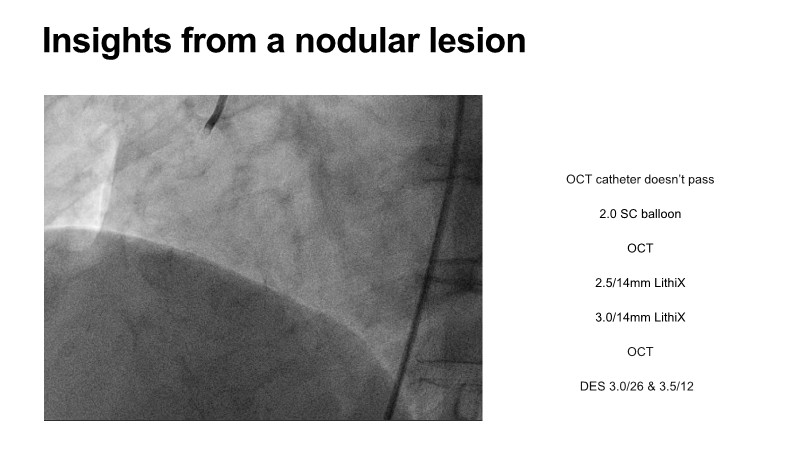

This EuroPCR 2025 session shares real-world insights confirming the promising results of the PINNACLE I trial, with LithiX IVL proving safe and effective across eccentric, concentric, and nodular calcifications.

Learn how this technology works, review the supporting evidence, and follow step-by-step case examples demonstrating optimal stent expansion and an efficient calcium modification workflow in daily practice.